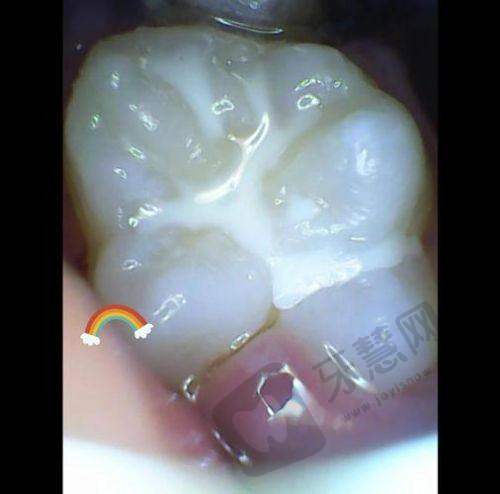

根管治疗实例:一位患者因牙齿疼痛前来就诊,经卫书盛医生检查后诊断为牙髓炎,需要进行根管治疗。卫医生为患者制定了详细的治疗方案,在治疗过程中,他操作熟练、手法轻柔,较大程度减轻了患者的痛苦。经过几次治疗后,患者的牙齿疼痛症状消失,修复了正常的咀嚼功能。

种植牙实例:另一位患者牙齿缺失,卫医生为其进行了种植牙手术,术后种植牙稳固,外观和功能都与真牙无异,患者对治疗成效非常满意。